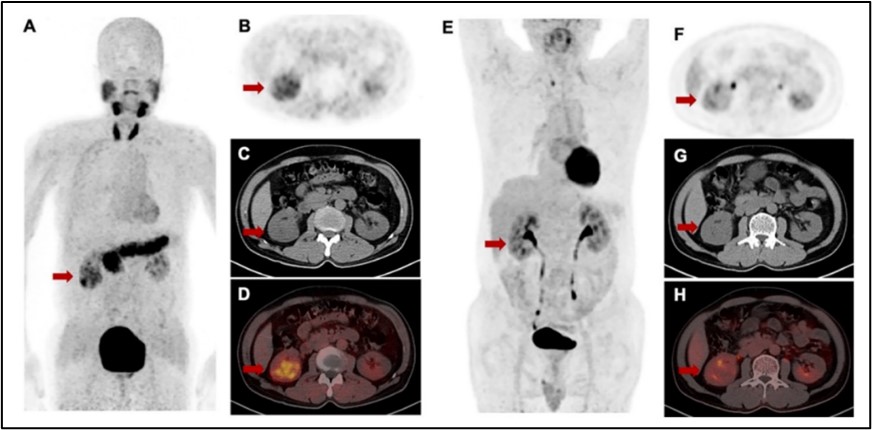

[18] Liang Zhao#, Bo Niu#, Jianyang Fang#, Yizhen Pang, Siyang Li, Chengrong Xie, Long Sun, Xianzhong Zhang, Zhide Guo*, Qin Lin, Haojun Chen*. Synthesis, preclinical evaluation, and a pilot clinical PET imaging study of 68Ga-labeled FAPI dimer. Journal of Nuclear Medicine 2022, 63:862-868.